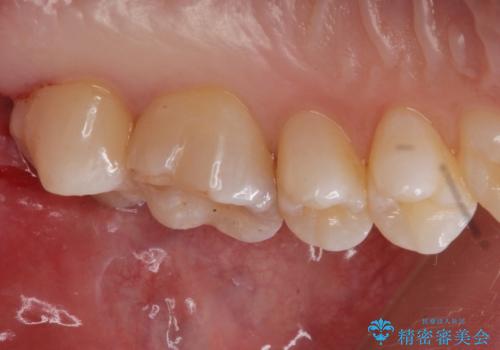

奥歯の治療の劣化が気になる。ザラザラしている

- 奥歯がザラザラして欠けている気がするとの事で来院。

古いプラスチックの詰め物がされていて、少し欠けていました。

拡大鏡下で古いプラスチックを除去して虫歯がないことを確認して

e-maxインレーにて治療しました。

白い詰め物が入り、ザラザラもなくなりました。

一つ手前の古いプラスチックで治療されている歯も現在詰め物にやりかえを検討中です。